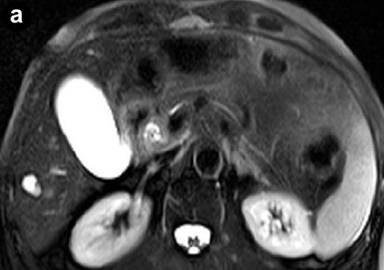

MR imaging was successively performed to evaluate and characterize the nature of the biliary stenosis by acquiring axial and coronal T1- and T2-weighted with/without fat saturation images integrated with MRCP T2-weighted hydro-cholangiographic sequences. In particular, the patient received 900 mL of superparamagnetic oral contrast material (Lumirem®, Guerbet, Paris, France) 20 min before the study. Post-contrast acquisition was performed after the intravenous administration of gadolinium diethylenetriamine pentaacetic acid (DTPA) in a volume of 20 mL with 2 mL/s acquiring T1 fast-field echo short-time inversion recovery (FFE-STIR) images. In particular, cross-sectional T1- and T2-weighted and MR cholangiography sequences showed dilatation of the biliary tree including the intrahepatic ducts, primarily of the left hepatic lobe and the common hepatic duct. Furthermore, MR images showed a lengthy stricture with luminal flow-signal preserved, irregular margins as well as abrupt and asymmetric narrowing in the middle third and intra-pancreatic segment of the common bile duct (Figure 1). A solid lesion along the common bile duct, at same level of the stricture, appearing as circumferential wall-thickening with a firm component projecting into the duct lumen, was also detected (Figure 2); after the administration of contrast medium, the lesion did not show significant enhancement in the arterial phase; however, late-phase images showed non-homogeneous enhancement (Figure 3). There was no evidence of positive lymph nodes or metastatic disease; the characteristics of the MR images were suggestive of a malignant primary stenosis probably by extra-hepatic cholangiocarcinoma. Furthermore, MR views demonstrated mild enlargement of the pancreas associated with a non-homogeneous signal intensity of the pancreatic tissue due to the presence of a hypointense nodule (Figure 3). A second ERCP examination was subsequently performed, which revealed a stricture immediately above and at the level of the intra-pancreatic common bile duct and the biliary stent was removed; brush cytology did not reveal atypical cells and the final report was not indicative of malignancy.

Figure 3. T1-weighted fast-field echo short-time inversion recovery (FFE STIR) post-contrast image shows a solid lesion with inhomogeneous late-phase enhancement (at the level of the intra-pancreatic biliary tract); moreover, MRI demonstrates mild enlargement diffusely involving the head of the pancreas associated with inhomogeneous signal intensity of the pancreatic tissue due to the presence of a hypointense nodule (arrow). |